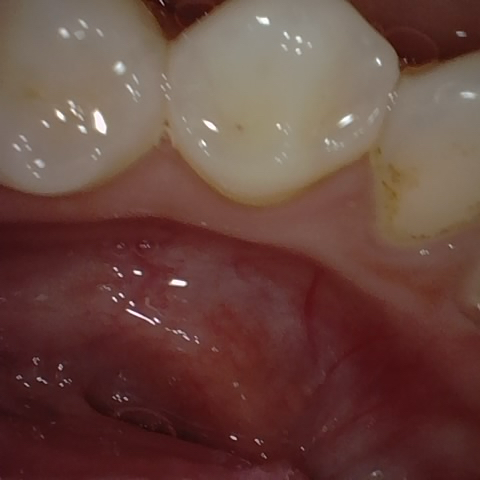

Image 4 / 52

NHD11205

Annotated as "Bad"

Original Image Rendering Image